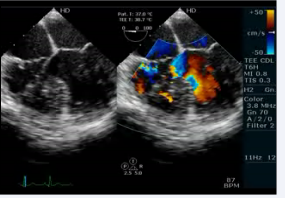

We performed transesophageal echocardiogram to define the anatomy and confirmed AV and VA concordance (video 4)

. The echocardiogram showed an elongated left ventricular outflow tract due to subaortic conus (Figure 4, video 5).

Figure 4: Transesophageal echocardiogram long axis view showing presence of subaorticconus with aortomitral discontinuity

Video 5: Transesophageal echocardiogram long axis view showing subaortic conus with aortomitral discontinuity.